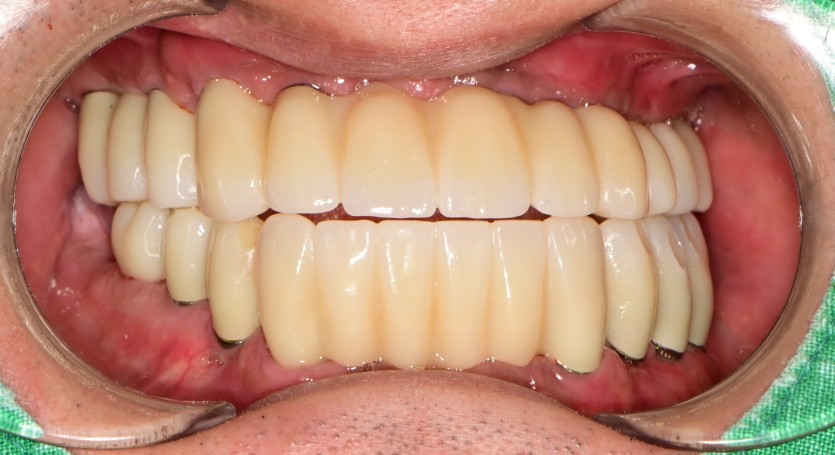

전체 임플란트 증례입니다.

18개의 임플란트로 완성하였습니다.